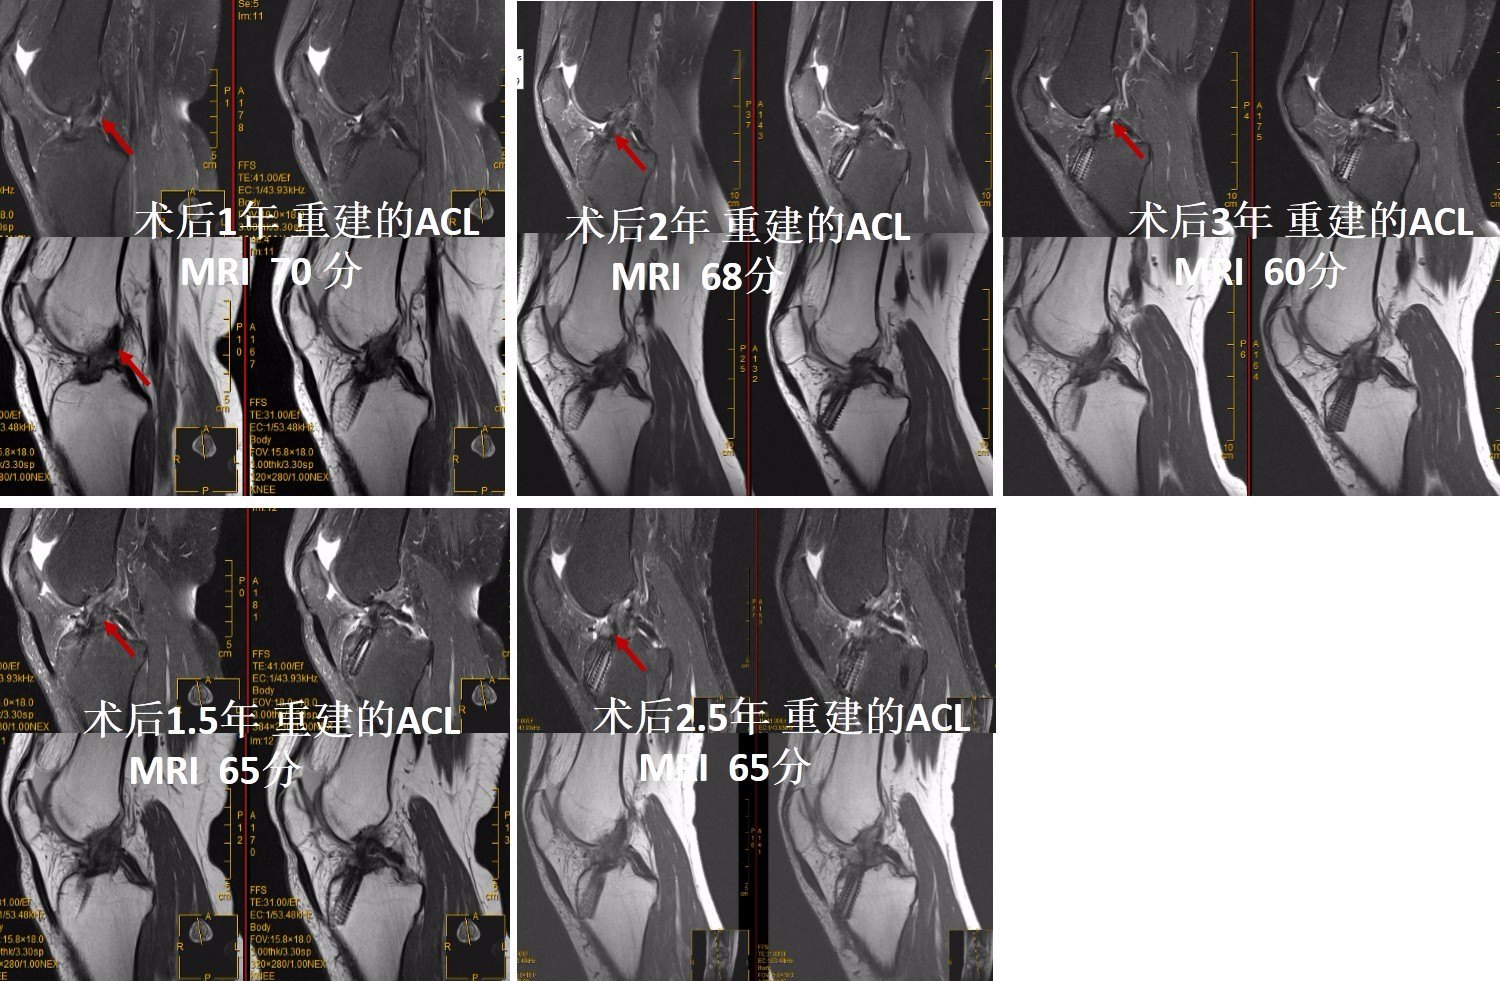

前交叉韧带重建后大部分韧带在术后1-2年愈合完好,韧带塑形成熟。

有些患者在前交叉韧带重建2年后,韧带塑形完好,但是如果不加控制的进行过强的运动,韧带也会出现变化,甚至变差!

当然,大部分患者进行前交叉韧带重建后,只要定期复查,在医生的指导下进行康复,韧带大多数是可塑性完好的。但是过程是缓慢的。大部分需要经历至少1年以上的塑形过程。

但是也存在一部分患者在进行前交叉韧带重建后,韧带塑形一直不满意,韧带塑形 变化不明显。术后2年一直韧带塑形变化一直无好转。